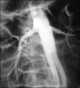

Bilaterally decreased renal contrast concentration